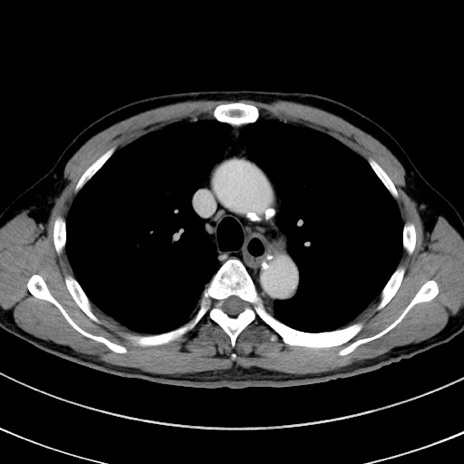

症例8(横断像)

【症例】 60歳代男性

【主訴】 黒色吐物

【現病歴】 4日前から嘔気自覚、2日前の朝食後にも嘔気あり、自分で手で嘔吐反射起こし嘔吐したところ血が混ざっていたため受診。

【既往歴】 5年前汎発性腹膜炎を伴う急性虫垂炎で手術、高血圧、前立腺肥大症、高脂血症

【身体所見】 腹部正中に手術癩痕あり 腹部平坦・軟圧痛なし膨満感あり

【データ】WBC 8400、CRP 4.54